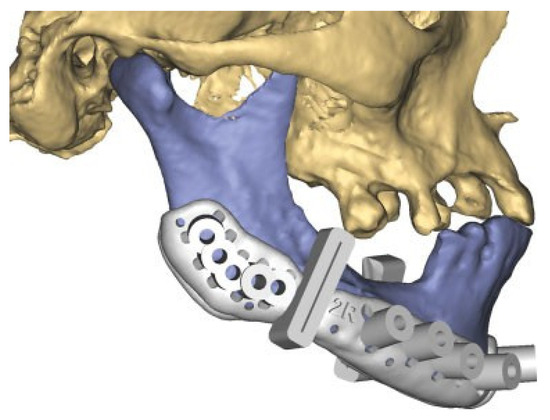

Figure 4.

After plate removal in the software, osteotomies in the fracture areas and corrective rotation of displaced fragments was performed to close the open bite and restore the occlusion in the virtual plan.